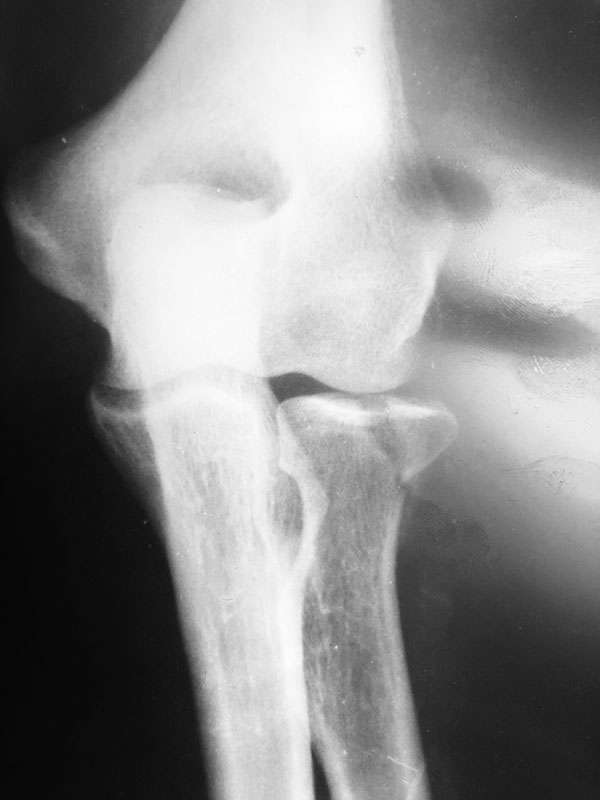

Перелом головки лучевой кости 1,5-месячной давности. Как быть?

Здравствуйте. Мужчина 50 лет. Травма 25 августа 2018 года. Рентген был расценён как ушиб (снимки прилагаются). В дальнейшем пациента беспокоила боль, ограничение подвижности.

Из поля зрения медицины выпал. При повторном обращении 9 октября выполнен повторный снимок- зам. консолидирующийся перелом головки луча. Подскажите пожалуйста с тактикой лечения.

P.S.:Собственно у пациента про- супинационные движения в полном объёме за исключением дефицита супинации в 10^ и сгибательная контрактура локтевого сустава около 15^. Все это время сустав без фиксации.